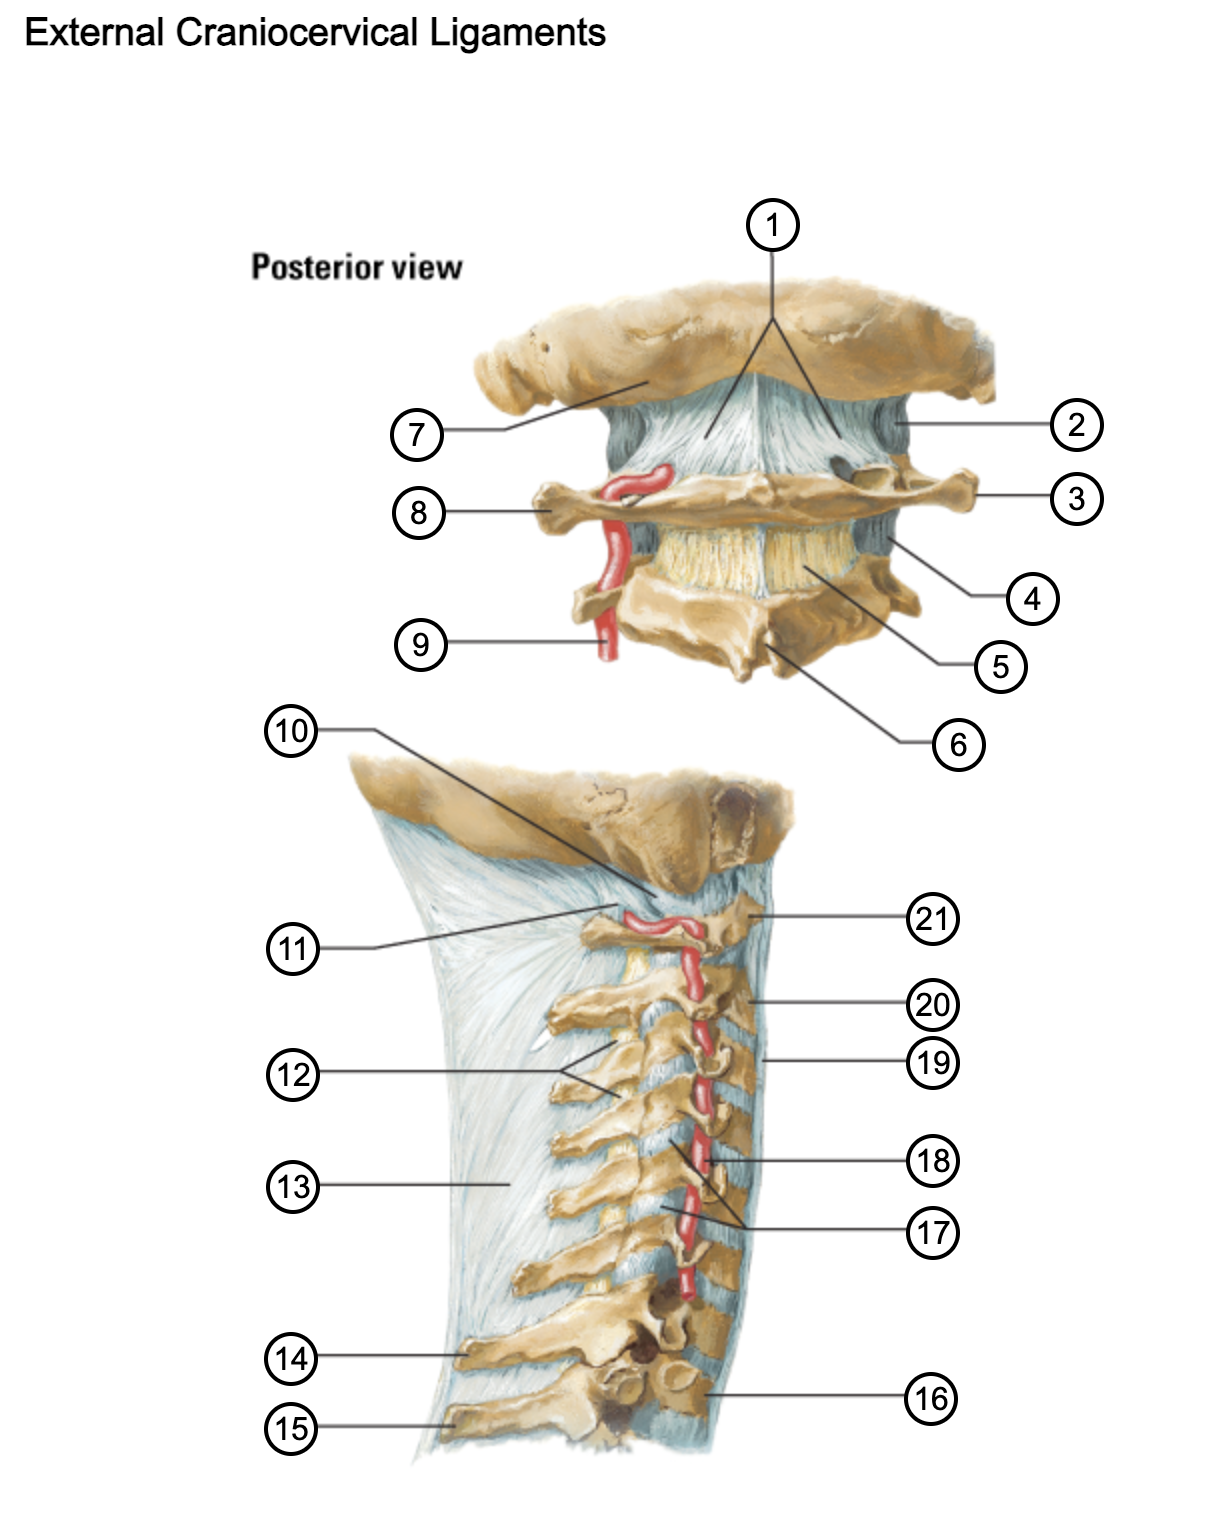

1

posterior antlantooccipital membrane

2

capsule of atlantooccipital joint

3

transverse process of atlas (C1)

4

capsule of lateral atlantoaxial joint

5

ligamenta flava

6

spinous process

7

occipital bone

8

transverse process of atlas (C1)

9

vertebral artery

10

capsule of atlantooccipital membrane

11

posterior atlantooccipital membrane

12

ligamenta flava

13

nuchal ligament

14

spinous process of C7 vertebra

15

spinous process of T1 vertebra

16

T1 vertebra

17

zygapophysical joints (C4-5 and C5-6)

18

vertebral artery

19

anterior longitudinal ligament

20

body of axis

21

Atlas (C1)